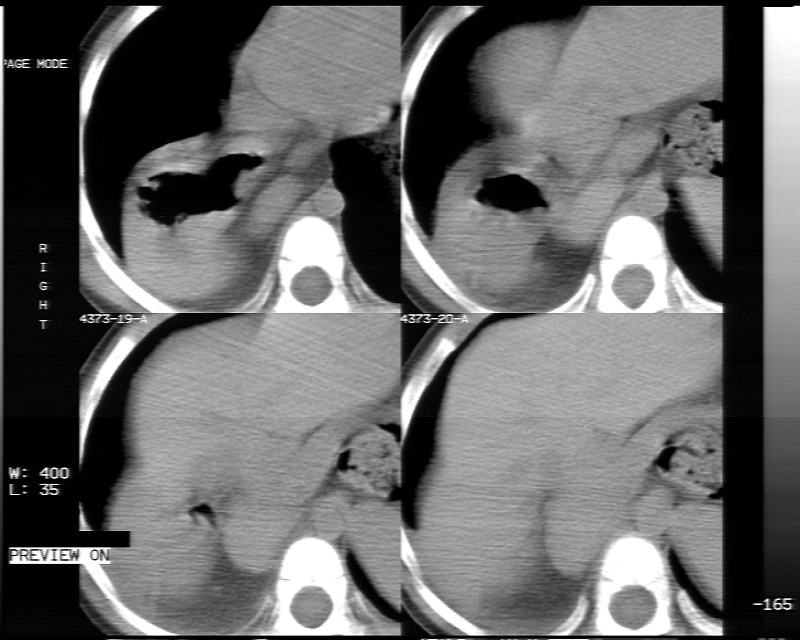

男性,3岁,斜疝术前常规检查胸片体检发现右下肺病变。咳嗽,无发烧。

内有气体,液平面,考虑食管裂孔疝可能性大。建议食道钡透。

有液气平面,前部肺纹理聚集(受压改变),周围肺野及相邻胸膜清晰,支持膈疝,可吞服造影剂看一下。

考虑膈疝(右侧胸腹膜裂孔疝?)。